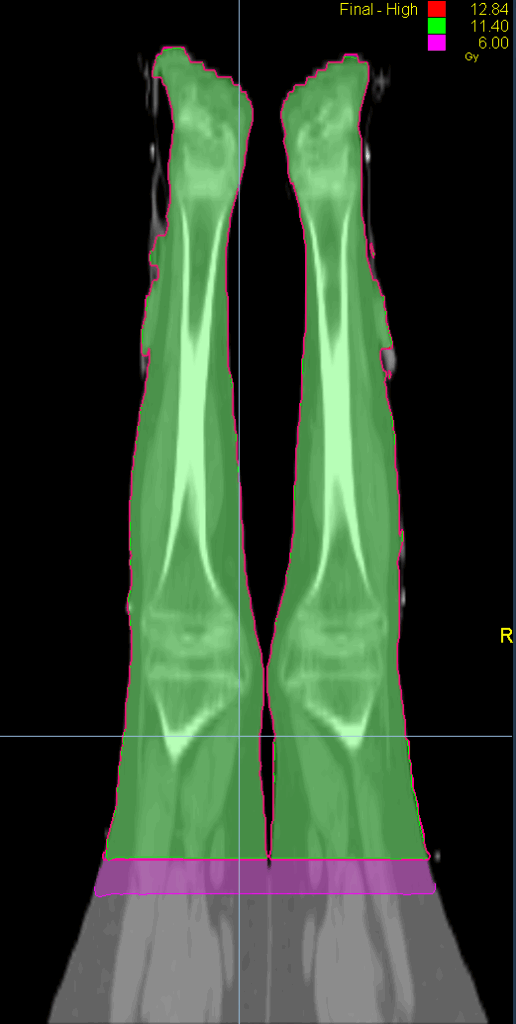

Treatment Plan Images

Fractionation / Protocol Used

12 Gy in 6 fractions